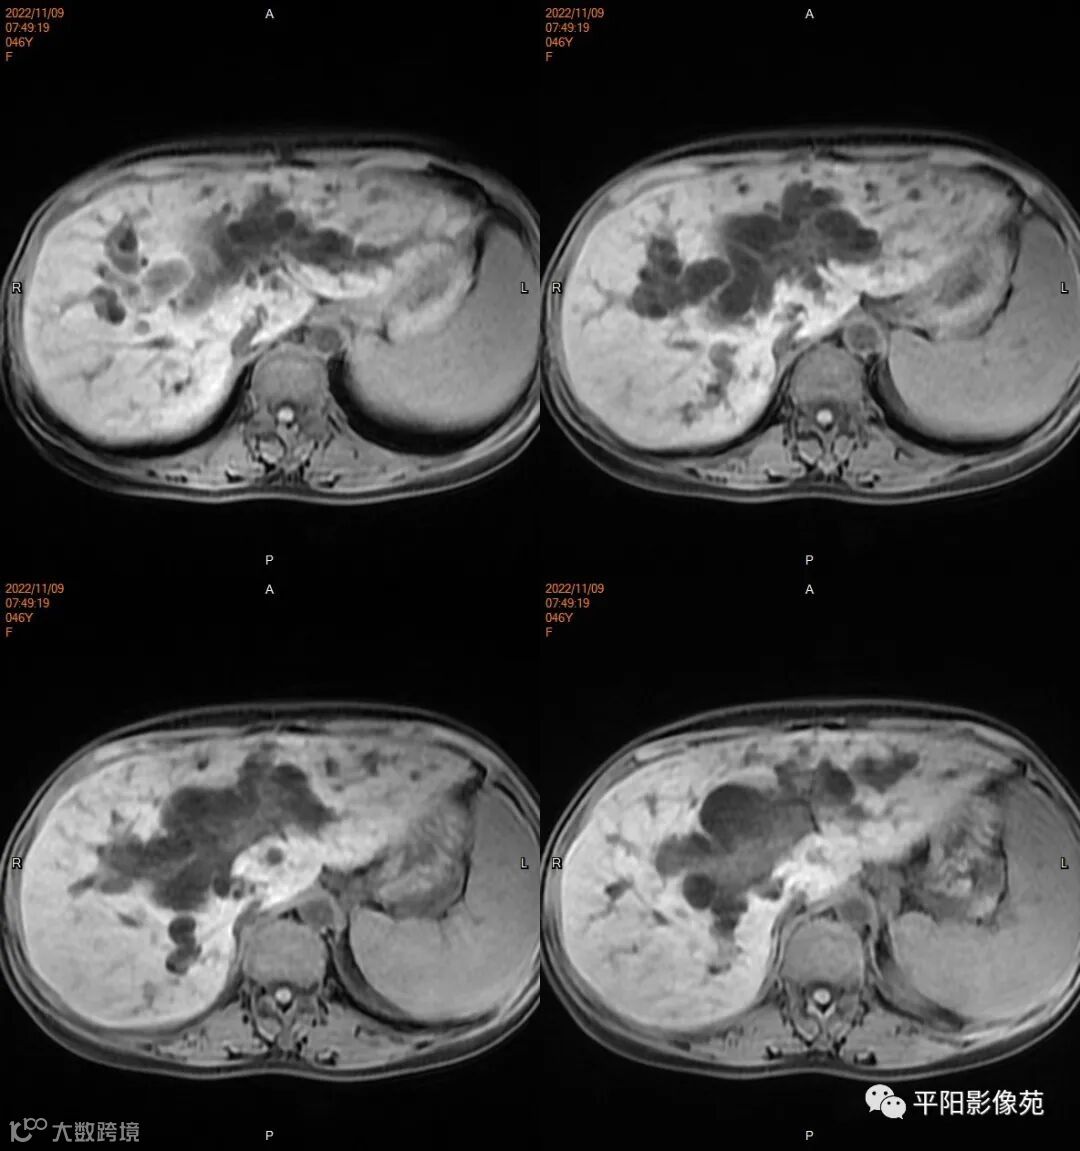

MR

肿瘤病理基础以肉眼形态分型可分为息肉型、溃疡型、缩窄型、弥漫狭窄型。

影像表现: